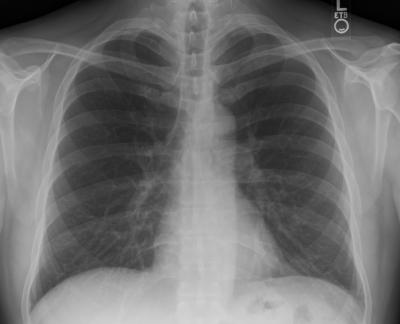

X-ray मार्फत आता कोरोना व्हायरसचं निदान होऊ शकतं. यामुळे खर्च आणि वेळ या दोन्ही गोष्टी वाचणार असल्याची माहिती मिळत आहे.

नाशिकमधील ईएसडीएस (ESDS) या आयटी कंपनीने एक सॉफ्टवेअर तयार केलं आहे. ज्यामुळे फक्त एक्स-रे (X-ray) मार्फत कोरोना व्हायरसं निदान करणं शक्य आहे.

कंपनीने दिलेल्या माहितीनुसार, ज्या व्यक्तीची टेस्ट करायची आहे, त्याच्या छातीचा एक्स-रे काढावा लागेल. या एक्स-रेची डिजिटल प्रिंट या सॉफ्टवेअरमध्ये लोड करावी लागेल.